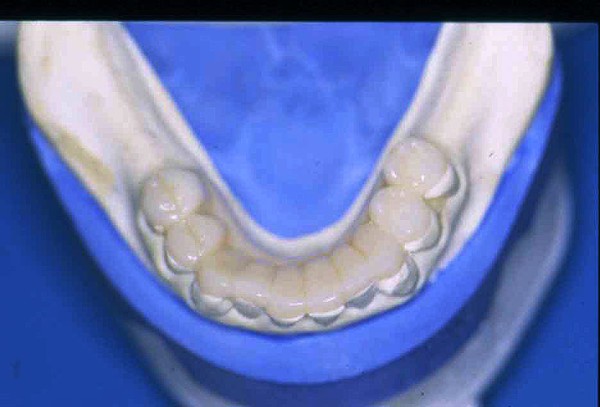

APRECIACIONES DIAGNÓSTICAS EN BASE A LA APERTURA MENTAL DEL CLÍNICO FRENTE A LO QUE EL PACIENTE PROPONE EN MUCHAS OCASIONES , LA DEMANDA DE LOS PACIENTES NOS INCLINAN A FOCALIZAR NUESTRA ATENCIÓN EN LAS PIEZAS DE LAS CUALES EL ENFERMO SE QUEJA. PACIENTE SEXO FEMENINO, 55 AÑOS, SE PRESENTA A LA CONSULTA DERIVADA POR COMPAÑERO GENERALISTA, QUIEN LLEVA MESES PROCEDIENDO A LA «DESINFECCIÓN» DE UN PRIMER PREMOLAR IZQUIERDO, EL QUE SE PRESENTA ABIERTO EN SU CONDUCTO EN EL AFÁN DE PERMITIR EL ESCAPE DE GASES DE UNA GANGRENA PULPAR. A LA INSPECCIÓN CLÍNICA SE OBSERVAN FACETAS PARAFUNCIONALES DE TERCER GRADO , ASINTOMÁTICAS, CON EVIDENTES DIFICULTADES MASTICATORIAS Y ESTÉTICAS , FALTA TOTAL DE SUS MOLARES INFERIORES, Y ADELANTAMIENTO PRONUNCIADO DE SU MANDIBULA, LA QUE CUESTA MANIPULAR DEBIDO A LA SITUACIÓN DE ESPASMO DE CASI TODA SU MUSCULATURA GNATICA. SE ESTUDIA EL CASO RADIOLOGICAMENTE, Y SE RELAJA EL SISTEMA MEDIANTE LAM. DE LONG REALIZANDO UN MONTAJE EN LA ORC OBTENIDA. NO SATISFECHOS CON EL RESULTADO, CONFECCIONAMOS UN JIG DE LUCIA, EL QUE DEJAMOS EN BOCA TODA UNA NOCHE, AL CABO DE LA CUAL REALIZAMOS UN NUEVO REGISTRO REALIZAMOS UN ENCERADO RÁPIDO DEL CASO, Y CONFECCIONAMOS UNA ESTRUCTURA OCLUSAL PLASTICA, QUE ADEMÁS REPONGA EL ASPECTO ESTÉTICO PERDIDO (FÉRULA DE RELAJACIÓN DE COMPONENTE ESTÉTICO), LO QUE PERMITE AL ENFERMO LUEGO DE DOS DÍAS DE USO, NO SOLO CORROBORAR LA COMODIDAD MASTICATORIA Y LA FALTA DE SÍNTOMAS MUSCULARES, SINO TAMBIÉN OBSERVAR APROXIMADAMENTE LA DIFERENCIA ENTRE LA SITUACIÓN INICIAL Y LO QUE PUEDE LOGRARSE MEDIANTE EL TRATAMIENTO. EL PACIENTE ADVIERTE LA MEJORÍA DE LA SITUACIÓN. ACEPTADO POR PARTE DEL MISMO EL TRATAMIENTO SUGERIDO, CREAMOS UN JUEGO COMPLETO DE PROVISORIOS EN BASE AL ENCERADO, Y PROCEDEMOS A TRATAR LA INFRAESTRUCTURA, QUE CONSISTE EN LAS ENDODONCIAS, SUS REFUERZOS A PERNOS DE ORO, LOS ASPECTOS PERIODONTALES DEL CASO, Y DOS IMPLANTES INFERIORES CON TÉCNICA SEMISUMERGIDA ,DE 5 MM DE ANCHO POR 12 DE LONGITUD, CON ANILLO DE ZIRCONIO , A LA ESPERA DE OSTEOINTEGRACIÓN, TRANSCURREN TRES MESES EN EL USO DE UNA NUEVA OCLUSIÓN CONSTITUIDA POR LOS PROVISIONALES, SEGÚN EL ENCERADO, QUE SE REALIZÓ SIGUIENDO LOS CÁNONES DE UNA OCLUSIÓN ORGÁNICA. COMPROBADA LA EFICACIA DE LA NUEVA SITUACIÓN, CON SUS DISCLUSIONES LATERALES Y POSTERO ANTERIORES CORRECTAS, CARECIENDO YA DE SINTOMATOLOGÍA MUSCULAR (SIN MIALGIAS, SIN MIOSITIS, Y CON UN GRADO DE APERTURA DE 4,50 CM), Y SIN SIGNOS EVIDENTES DE DESGASTE SOBRE EL MATERIAL DE LOS PROVISORIOS, ES DECIR: VERIFICANDO QUE EL PACIENTE YA NO BRUXA, VERTICALIZANDO EL CICLO MASTICATORIO /OTORGANDO ORC/ DIMENSIÓN VERTICAL /PROTEGIENDO A LAS PIEZAS `POSTERIORES DE IMPACTOS LATERALES RECIEN ENTONCES , MONTAMOS EN ARTICULADOR SEMI AJUSTABLE LOS MODELOS DE TRABAJO DEFINITIVOS. CONFECCIONAMOS ENTONCES LAS COFIAS INFRA PORCELANA, EN PORCELANA DE ALTA DENSIDAD EN EL SECTOR ANTERIOR Y EN ORO GALVÁNICO PARA EL SECTOR POSTERIOR PARA LUEGO COMPLETAR LA GUIA ANTERIOR , VERIFICANDO LA ALTURA DE LOS INFERIORES RESPECTO DEL LABIO INFERIOR Y CORROBORANDO LOS PUNTOS DE CONTACTOS INTER CANINOS, QUE CENTRALIZAN LA MANDIBULA Y VERTICALIZAN EL CICLO MASTICATORIO Y LAS DISCLUSIONES CANINAS QUE OTORGARÁN PROTECCIÓN A LOS SECTORES POSTERIORES. POSTERIORMENTE CHEQUEAMOS LA DISCLUSIÓN EN PROPULSIVA DE LA GUIA ANTERIOR YA TERMINADA. FIG38 FIG39 UNA VEZ OBTENIDO UN COMANDO ANTERIOR EFECTIVO, COMO LO ES LA GUIA ANTERIOR CON TODOS SUS COMPONENTES, PROCEDEMOS A REALIZAR LAS TABLAS PREMOLAR / MOLAR DE AMBOS LADOS Y OBSERVAMOS QUE LOS PUNTOS INTEROCLUSALES DE CONTACTO SEAN SUFICIENTES Y CUMPLAN SU OBJETIVO DE OTORGAR ESTABILIDAD MESIO DISTAL Y VESTÍBULO LINGUAL. TRANSCURRIDO UN AÑO DE FINALIZADO EL TRATAMIENTO, REALIZAMOS UN CHEQUEO POST OPERATORIO DEL CASO, EN TODOS LOS PARÁMETROS ANTERIORMENTE MENCIONADOS, Y OBSERVAMOS LA ABSOLUTA ESTABILIDAD DEL MISMO EN TODOS SUS NIVELES Y TEJIDOS.